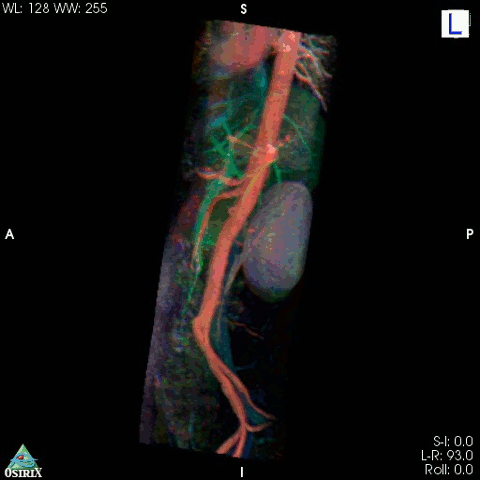

4. Kolorizovaná 3D snímka žíl a tepien